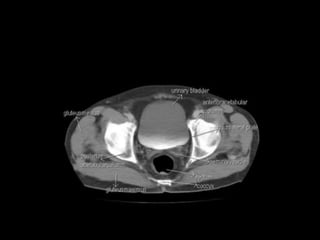

Pelvic peritoneal space Thepelvic peritoneal space is the inferior reflection of the peritoneum over the fundus of the urinary bladder and the front of the rectum at the junction of its middle and lower thirds. In females, the reflection is also over the anterior and posterior surface of the uterus and the upper posterior vagina.In males there is only one potential space for fluid collection posterior to the bladder, the rectovesical pouch. In females there are two potential spaces posterior to the bladder, the uterovesical pouch, and posterior to the uterus the deeper rectouterine pouch (pouch of Douglas). The layers of peritoneum on the anterior and posterior surfaces of the uterus are reflected laterally to the pelvic side walls as the broad ligaments, containing thefallopian tubes.